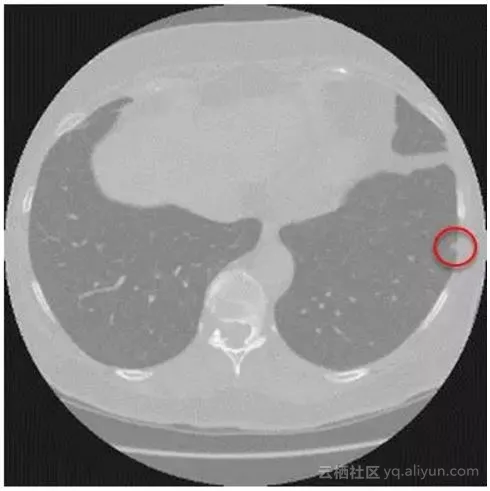

医疗大数据平台零氪科技为大赛提供经脱敏处理并由专家标注的高清胸部CT扫描影像数据。选手需要通过原始CT影像图片训练模型算法得到结节特征,最终实现对影像图片结节区域的智能化判断。

结节是影像学上的一个描述性名词,只有在发现结节之后才能进一步确认是良性还是恶性。

因此,对于肺癌的筛查来说,准确发现结节是诊断的第一步。

计算机结节检测系统通过学习大量有经验医师标注的样本,能在短时间内快速提升诊断能力,辅助基层医疗机构的医生减少误诊。